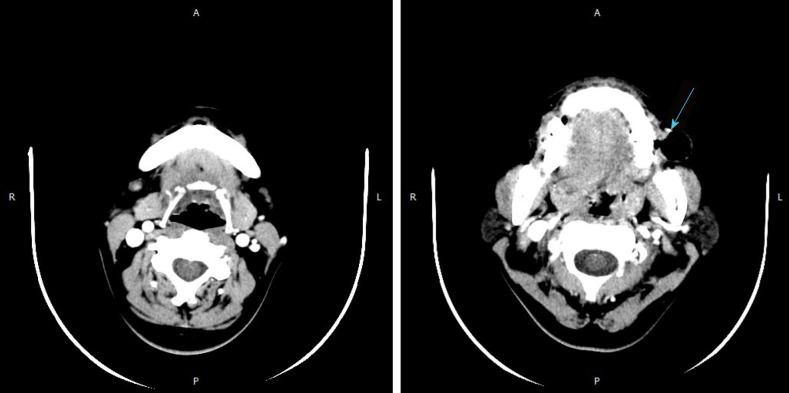

This report describes a rare case of diverticulum presenting in the buccal mucosa in a 44-year-old woman that was initially diagnosed in Stomatology Hospital, Wuhan University. We made our diagnosis under the guidance of imaging data, and the patient underwent surgical resection.

This report is the first confirmed case of buccal mucosal diverticulum. in addition, we elucidated that in general, idiopathic developmental abnormalities caused by succinate muscle defects are responsible for diverticulum development.